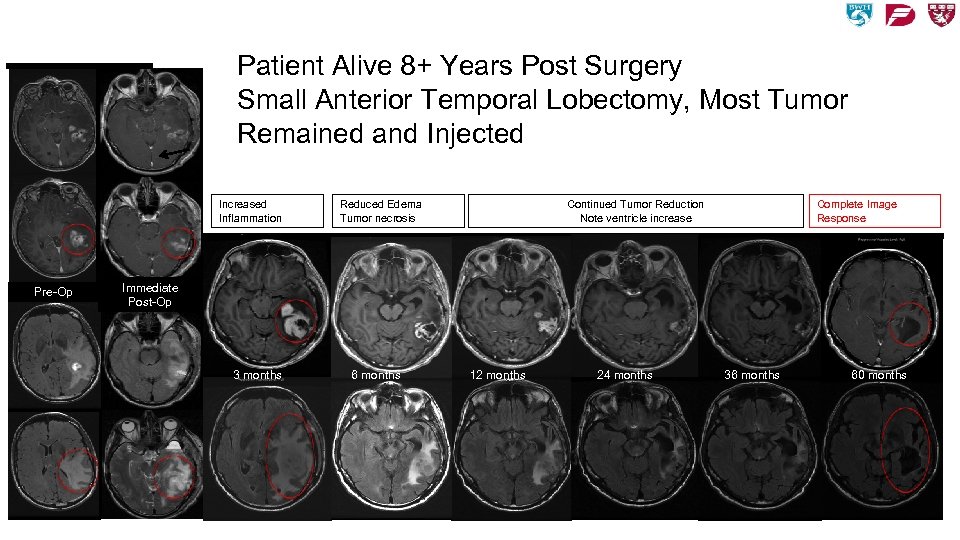

Prolonged Immune Surveillance! Patient Alive 8+ Years Post Surgery Small Anterior Temporal Lobectomy, Most Tumor Remained and Injected Increased Inflammation Pre-Op Continued Tumor Reduction Note ventricle increase Reduced Edema Tumor necrosis Complete Image Response Immediate Post-Op 3 months 6 months 12 months 24 months 36 months 60 months